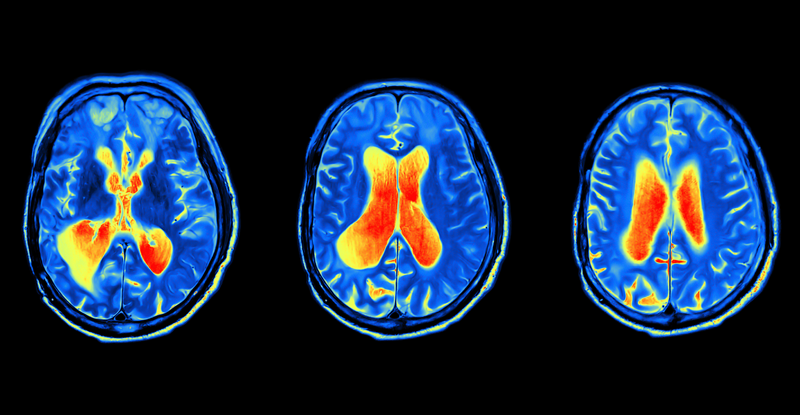

Electroencephalogram 'EEG'

non-invasive neuroimaging technique used to record the electrical activity of the brain

Functional Magnetic Resonance Imaging 'fMRI'

neuroimaging technique used to measure brain activity by detecting changes in blood flow and oxygen levels